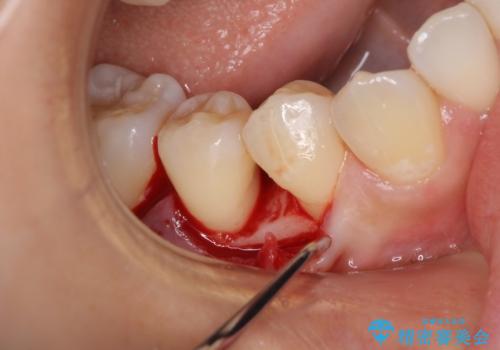

患者様は、他院で右下の歯を抜歯かもと言われました。全体の歯周病はなく、右下の1歯だけ骨が極端に減少していました(初診時歯周ポケット7mm。通常は3mm以下。)。その歯だけ咬合が強いことが原因と考えられたため、咬合を弱くする処置と減少した骨を再生する処置が必要になりました。

骨の再生治療手術をして10か月経過観察をしたのち、骨を平坦化する手術を行い、治療終了となりました。